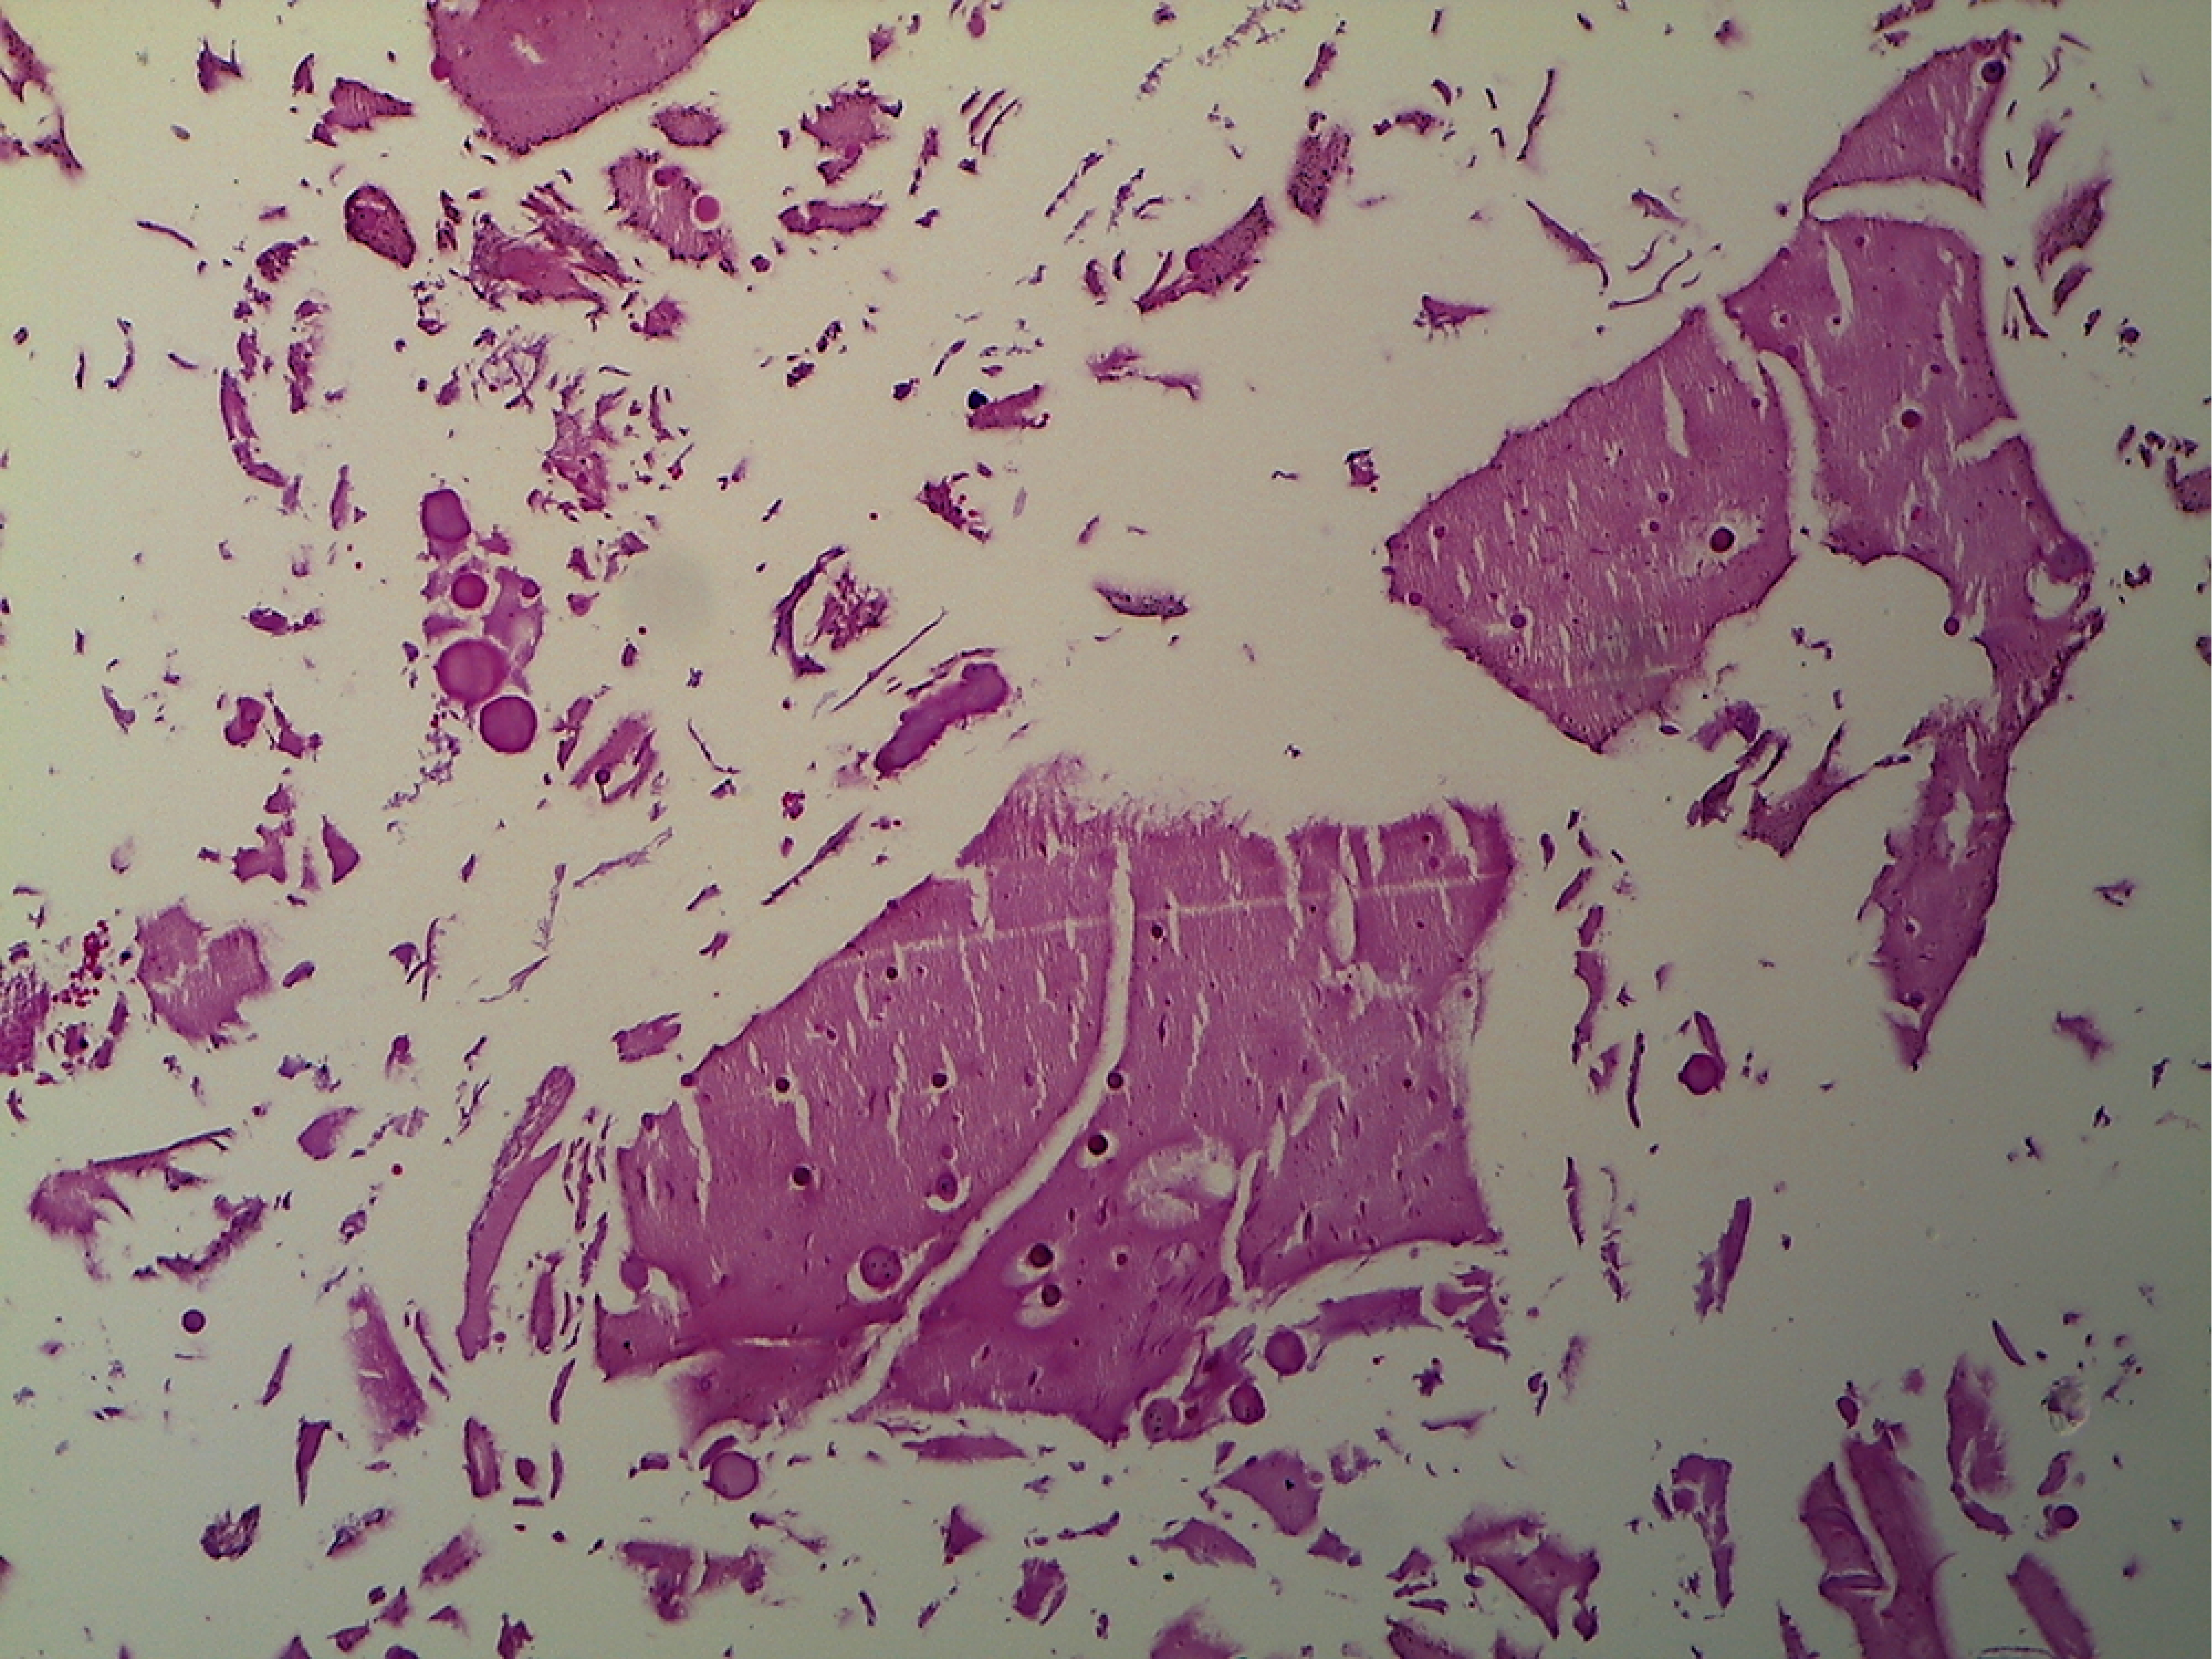

Tras completarse el protocolo de estudio con valoración por Servicio de Endocrinología, y sin contraindicación de evento quirúrgico, se programó para cirugía con diagnóstico presuntivo de adenoma hipofisario. Se realizó cirugía electiva el día 11 de marzo de 2016, a través de abordaje transesfenoidal directo, más resección de la lesión, más drenaje de absceso selar con hallazgos transoperatorios, lesión blanquecina aspirable, poco sangrante, de consistencia blanda y friable, acompañada de salida de material purulento y sangrado de 50 mililitros (Figura 2). Se enviaron muestras para cultivo de material, así como muestra a definitivo de lesión selar, con desarrollo bacteriano Staphylococcus aureus y reporte histopatológico de quiste de la bolsa de Rathke (Figuras 3 y 4). Se interconsulta al Servicio de Infectología que indica doble esquema de antibiótico a base de ceftriaxona y metronidazol.

Histopatología. El estándar de oro es el análisis histopatológico. A veces, tras el drenaje del quiste, puede ser difícil obtener una muestra quirúrgica de la pared quística. En el análisis rutinario de hematoxilina y eosina, se muestra un epitelio columnar o cuboidal simple con células caliciformes ciliadas o mucinosas. También se observan con frecuencia células columnares pseudoestratificadas.

Figura 3

Figura 4